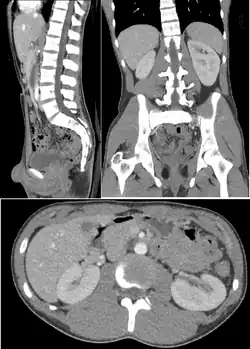

Abdomen and pelvis

CT is an accurate technique for diagnosis of abdominal diseases such as Crohn's disease,[66] GIT bleeding, and diagnosis and staging of cancer, as well as follow-up after cancer treatment to assess response.[67] It is commonly used to investigate acute abdominal pain.[68]

Non-contrast-enhanced CT scans are the gold standard for diagnosing kidney stone disease.[69] They allow clinicians to estimate the size, volume, and density of stones, helping to guide further treatment; with size being especially important in predicting the time to spontaneous passage of a stone.[70]